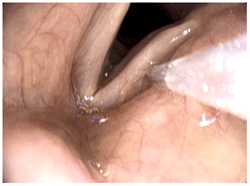

In-Office Vocal Fold Injection Augmentation exampleThe patient is seated in an exam chair in our procedure room at the Voice and Swallowing Disorders Center. The nose and throat areas are numbed with medication that is sprayed into the nose or mouth, nebulized into the mouth like an asthma medication, or dripped onto the throat with the scope used during the procedure.

A flexible camera scope is passed into the nose to bring the larynx (voice box) into view. It is normal to cough or feel a choking sensation during this part of the procedure. As your throat becomes numb, you may have the sensation that your throat is swollen and it may feel difficult to swallow. These sensations are an absolutely normal phenomenon and will soon subside as the anesthetic begins to wears off after the procedure. A very small needle is used to deliver the injection filler material, either through the mouth or through the skin of the neck. You may be asked to speak during the procedure to determine the exact amount of material needed to close the gap between the vocal folds.